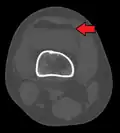

-

Lipohemarthrosis (presence of fat and blood from bone marrow in the joint space after an intraarticular fracture) seen on X-ray in a person with a subtle tibial plateau fracture -

Lipohemarthrosis due to a tibial plateau fracture -